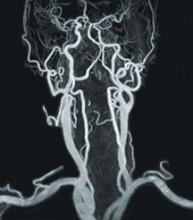

When Claude Bernard inserted a mercury thermometer into the carotid artery of a horse to measure blood temperature in 1844, little did he know he was laying the foundation for present day catheter angiography. Even though his practices were rudimentary compared to today’s standards, and it was not until 1929 that basic radiographic methods were implemented, he provided a stepping-stone into the current world of catheters and in turn, vascular imaging.